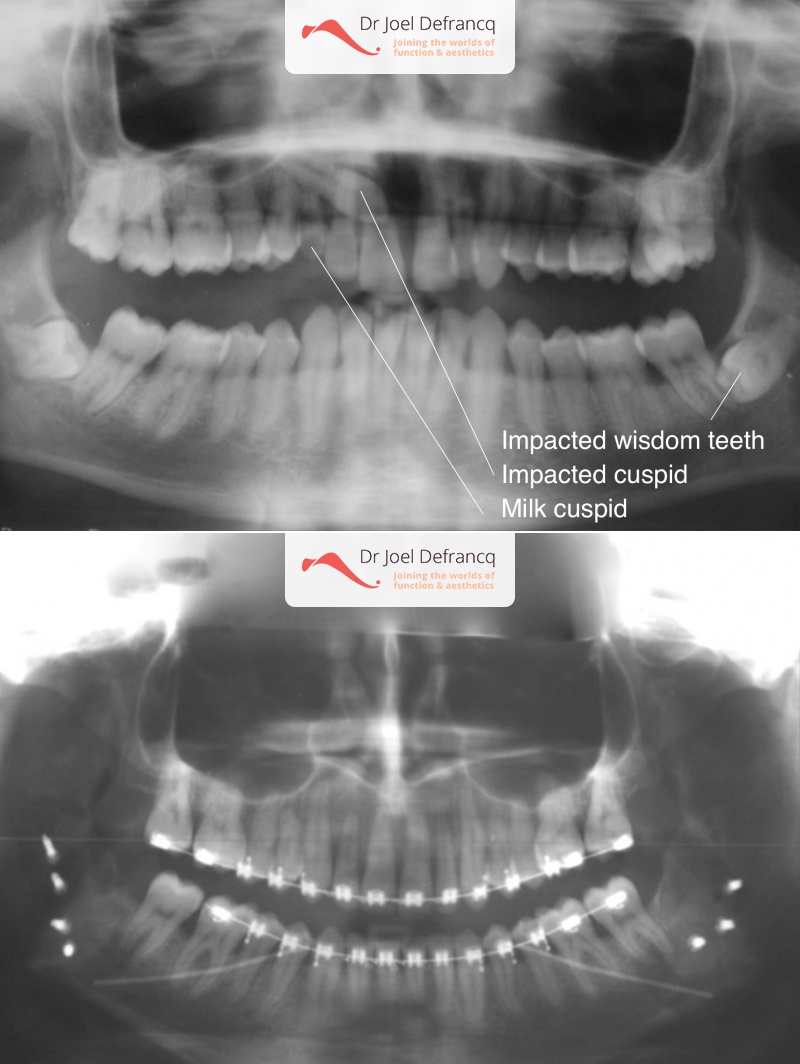

Dentale diagnose

- Klasse II divisie 2

Kaakchirurgie

- Verlenging onderkaak (BSSO)